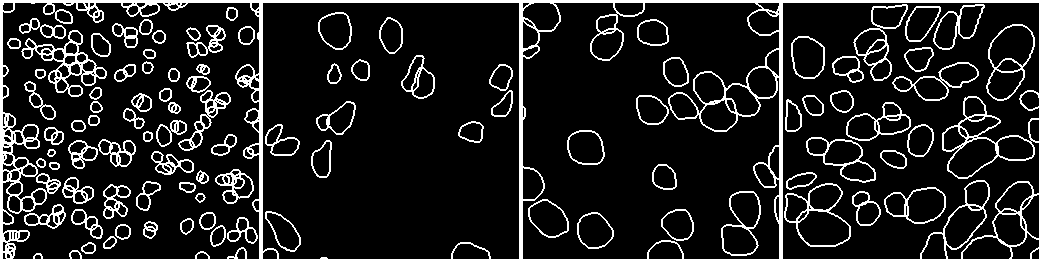

Case Study 5: Nuclei Segmentation

Nuclei segmentation is one of the basic pathology tasks in medical image analysis, whether it is traditional, [89], or deep learning-based, [90, 91, 92]. The diagnostic of pathology images is based on many terms representing objects, such as nuclei, cells, glands, and so on. Researchers extract features from these objects and use them for higher-level diagnosis. For example, tasks such as mitosis analysis, depend on nuclei segmentation and detection, because the classification of mitosis is based on the nuclei. We use a U-Net based model ([61]) to segment the nuclei on the dataset described in [50].

VI-1 Workflow

As shown in Fig. 17, the workflow includes six stages. The input loads the data from the dataset. The pre-processing converts formats and normalizes the stain of the pathology image. The dataset management splits the dataset into two sets, while the neural network uses the training set to train the model and uses the testing set to validate it.

The post-processing handles the results of the segmentation. It uses the binary normalization algorithm to improve the segmentation. The visualization tool depicts the final results to the user.

VI-4 Result and Visualization

The best result of the hyper-parameters is chosen as the final result. The DPUnet network is used as the model, and the dice function is selected as the loss function. The model is trained using 172 epochs with as the learning rate. The metric, namely AJI, reaches 0.6073, and the segmentation of the nuclei is shown in Fig. 19, while the AJI metrics of different organs are shown in Table III.

Organ | Breast | Liver | Bladder | Colon |

AJI | 0.6517 | 0.5310 | 0.6543 | 0.5424 |

Organ | Prostate | Stomach | Kidney | Mean |

AJI | 0.6147 | 0.6437 | 0.6135 | 0.6073 |